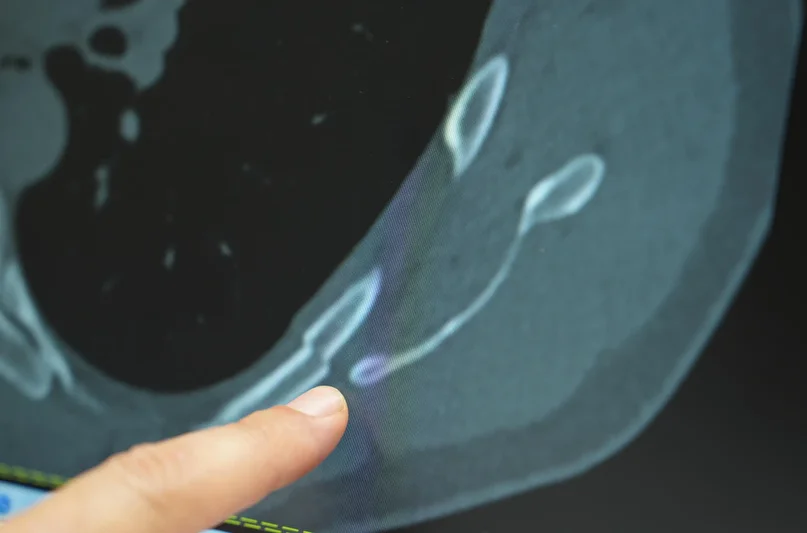

Uzman isim uyardı: Öksürürken kaburgalarınız kırılabilir

Göğüs ağrısı deyince akla yaşlılar gelir ama son dönemde gençlerde de öksürük sonrası kaburga kırıkları artış gösteriyor. Medipol Bahçelievler Hastanesi’nden Göğüs Cerrahisi Uzmanı Prof. Dr. Güven Sadi Sunam, genç yaşta görülen kaburga kırıklarının ardındaki gizli tehlikeleri ve korunma yollarını paylaştı.